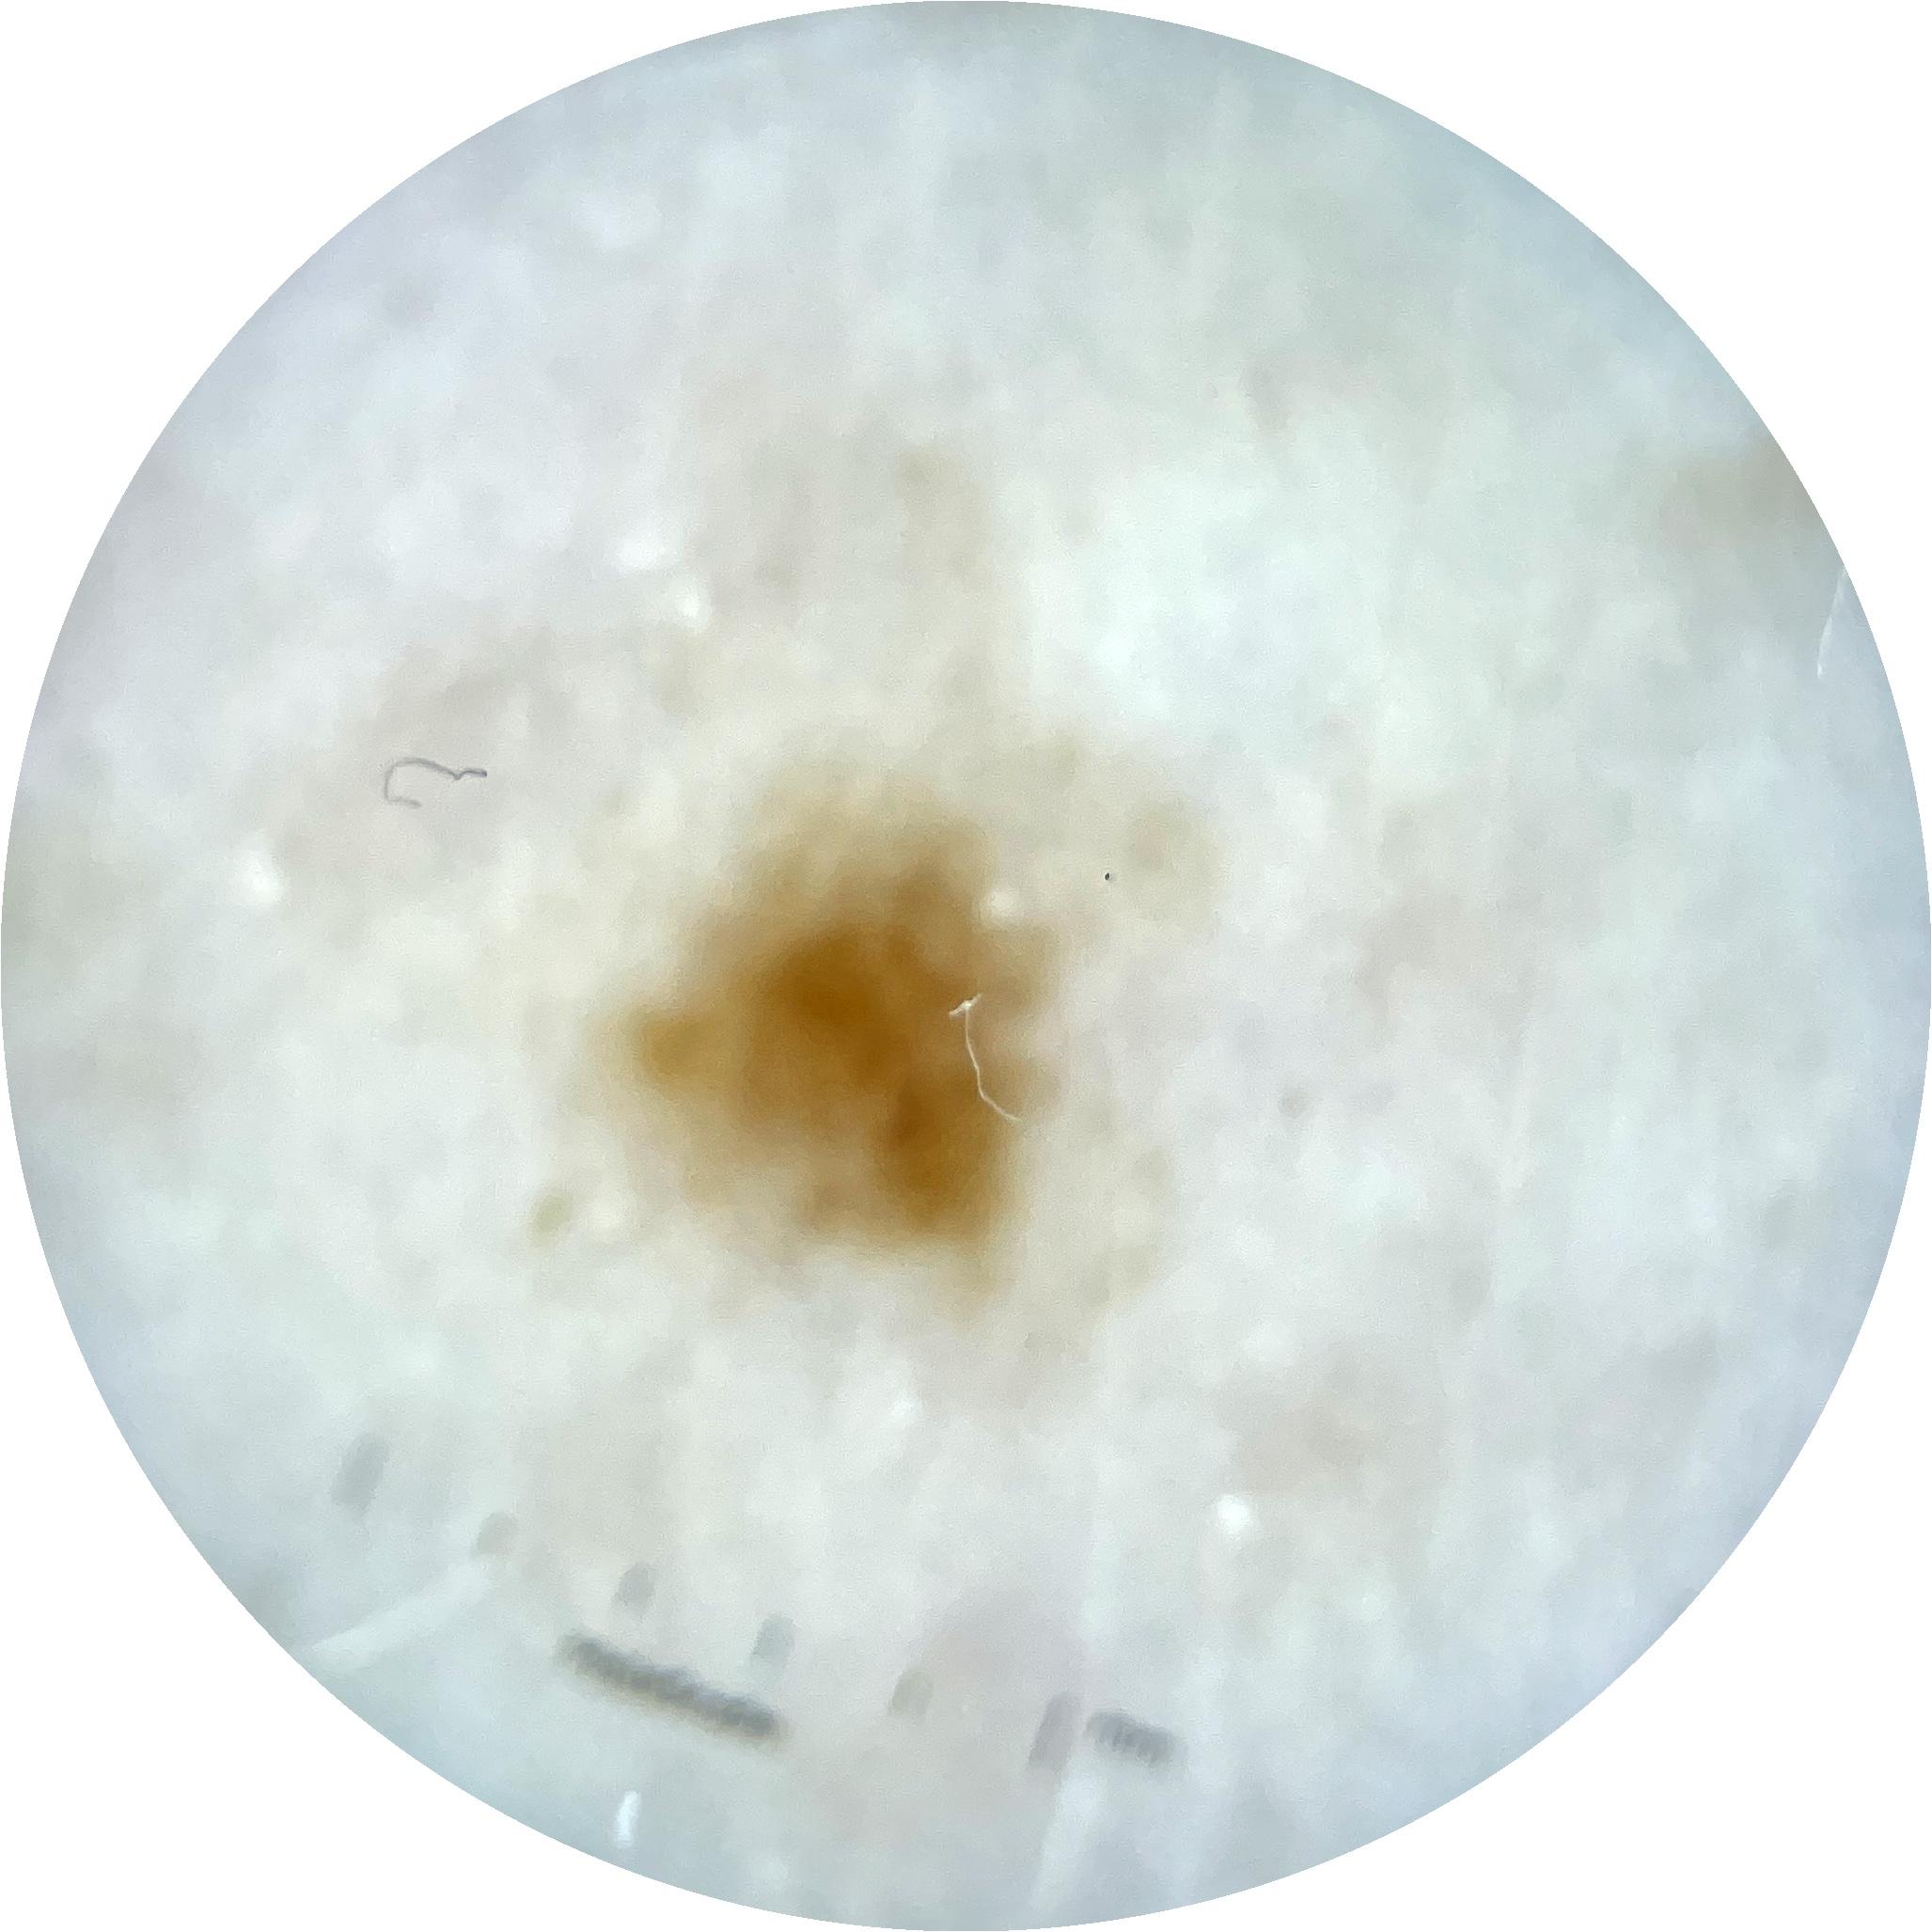

ISIC_9785574

Information

2003 x 2003

Attribute to

MEL-SELF Trial, https://www.sydney.edu.au/medicine-health/our-research/research-centres/melself-project.html

Field Value

acquisition_day 148

age_approx 45

anatom_site_1 Head and neck

anatom_site_general head/neck

concomitant_biopsy False

diagnosis_1 Benign

diagnosis_confirm_type single image expert consensus

family_hx_mm True

image_manipulation instrument only

image_type dermoscopic

lesion_id IL_0236417

patient_id IP_8456088

personal_hx_mm True

sex female